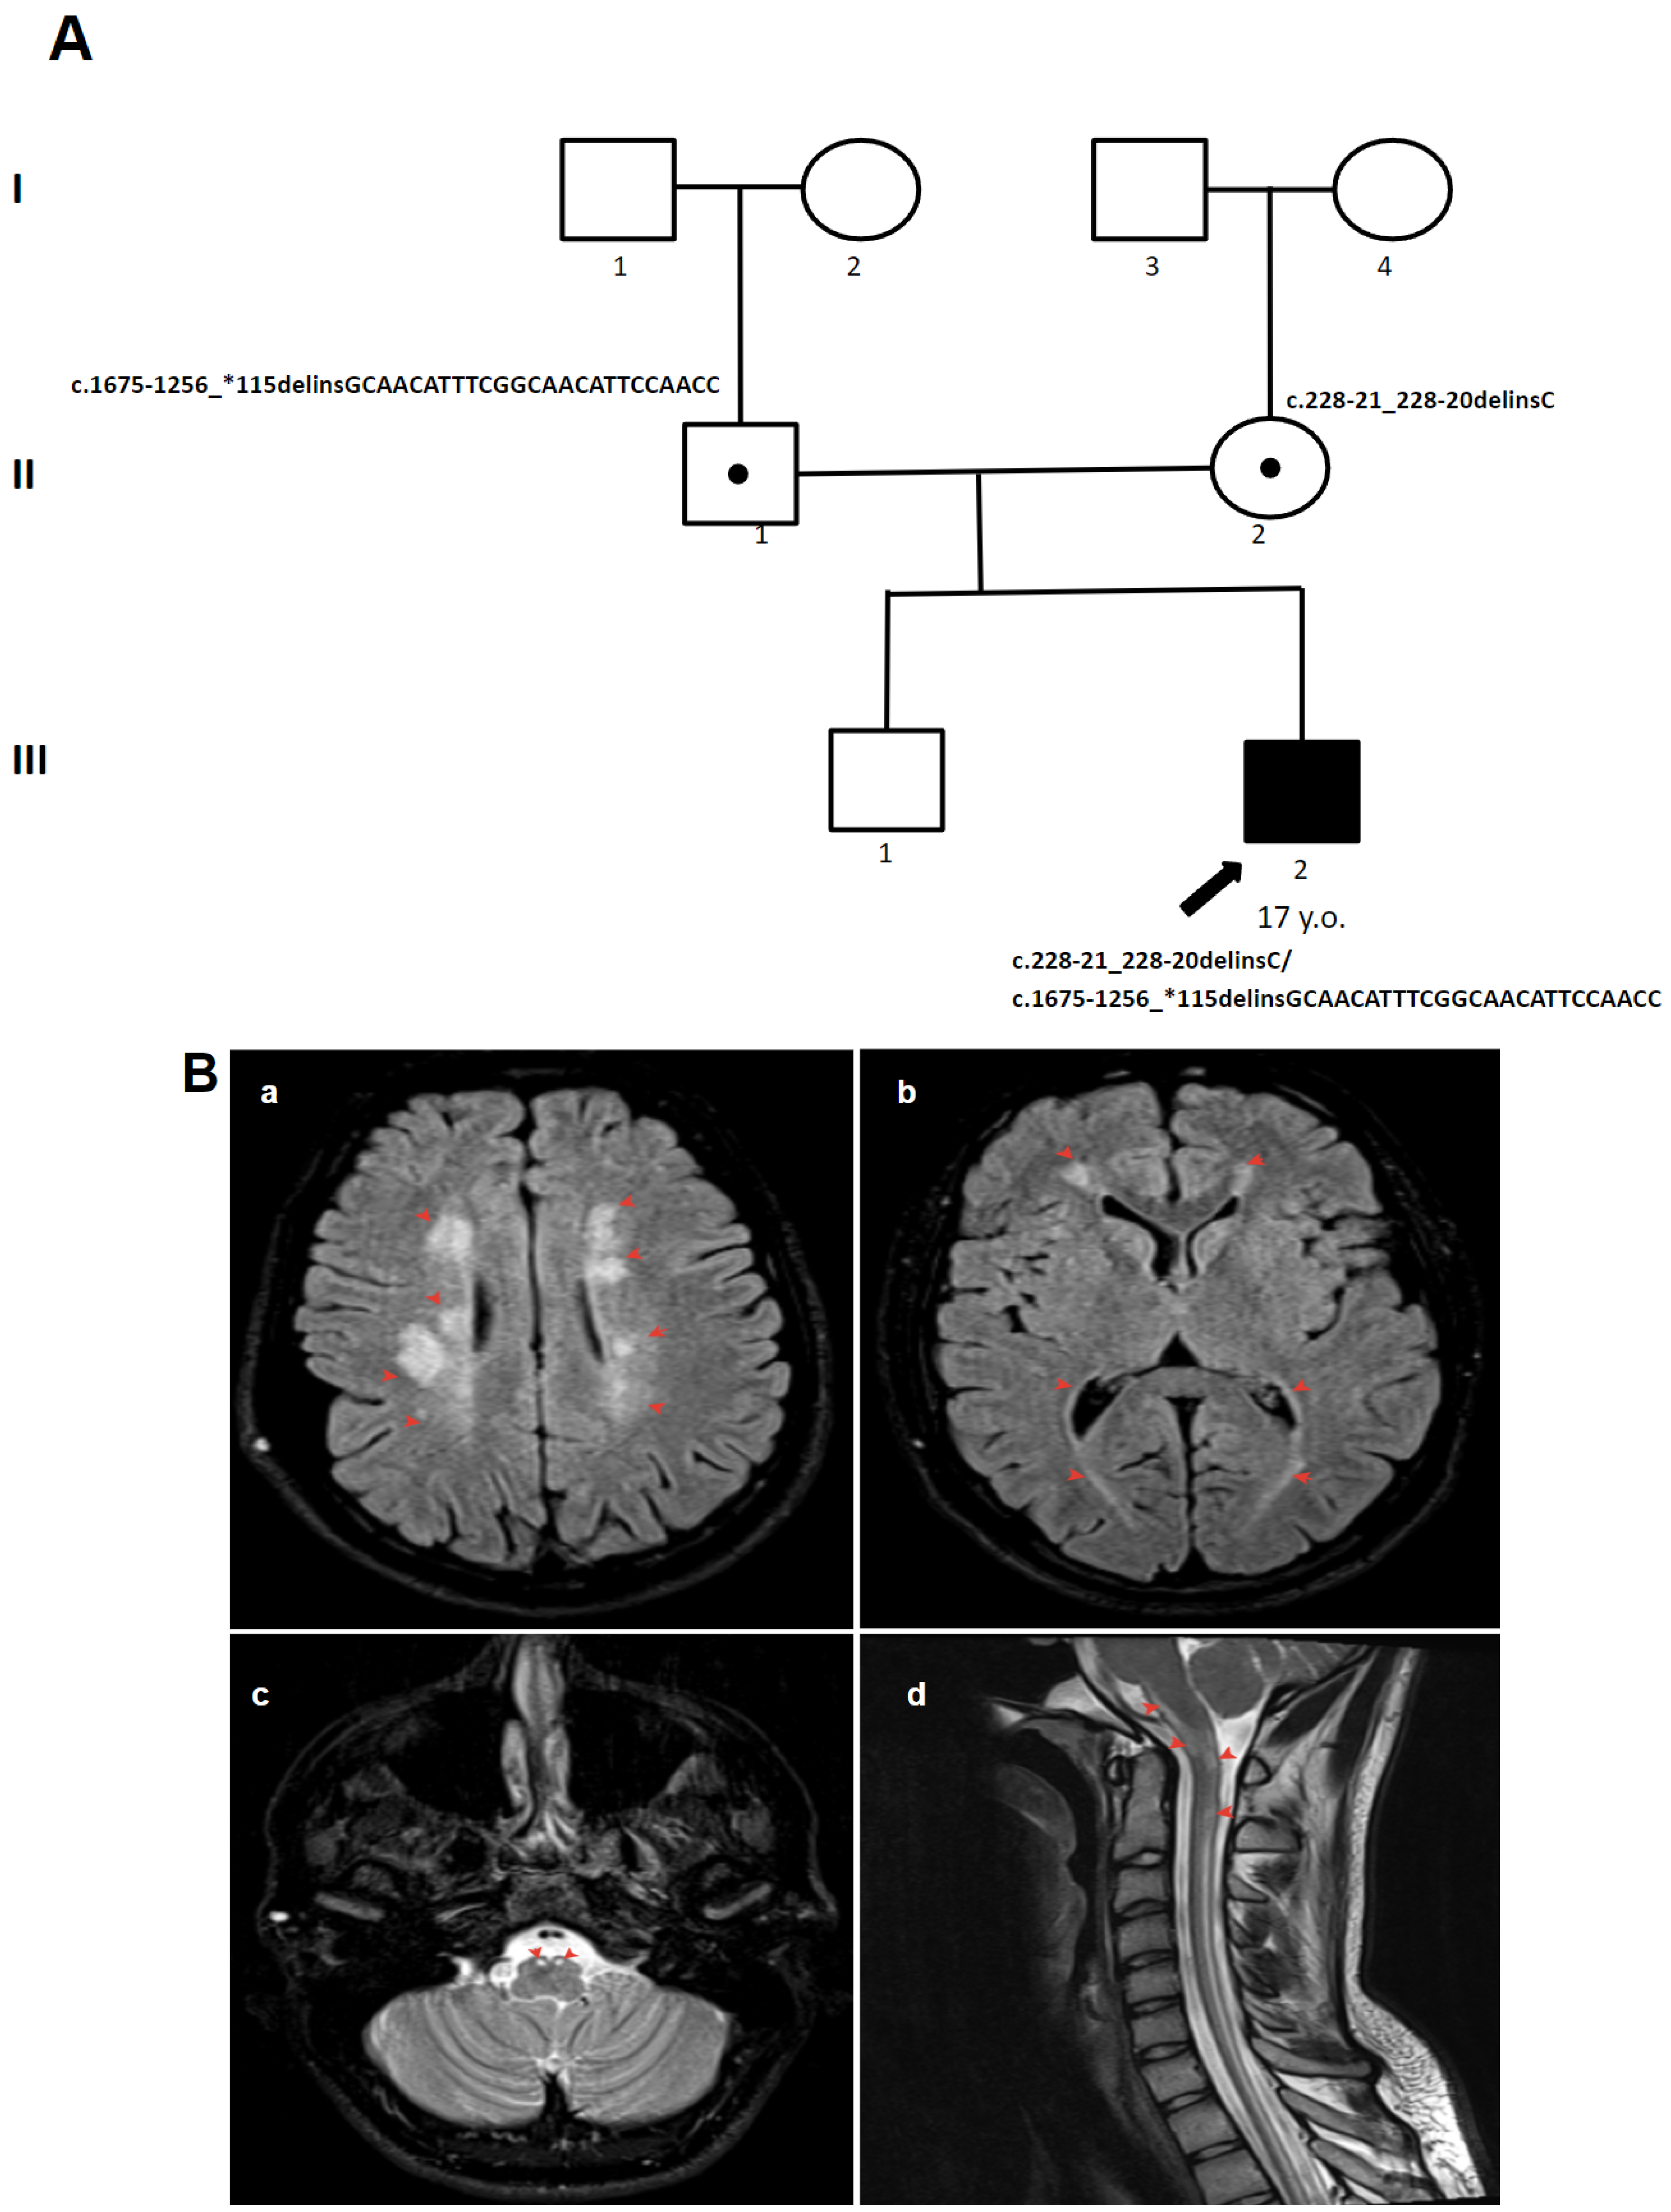

3.1.4. Patient 4